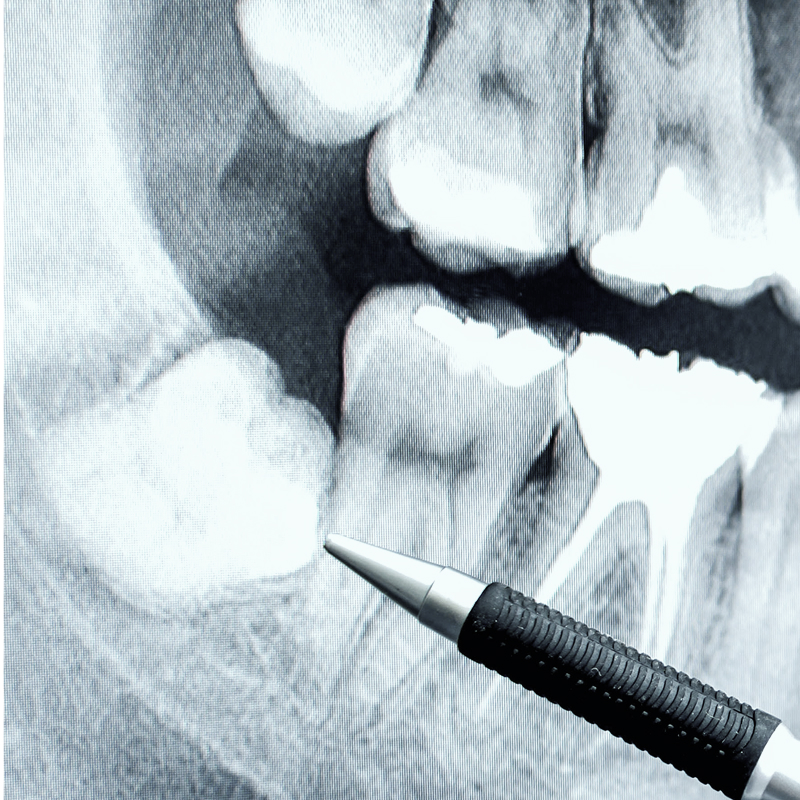

The best way to determine if you need a wisdom tooth extraction is by having your teeth and jaw examined by an experienced dental professional. Dentists use a combination of X-rays and physical dental exams to determine if a patient needs their wisdom teeth removed. Some patients will feel pain or soreness if their wisdom teeth are beginning to cause issues, while others won’t have any noticeable symptoms. Our team will monitor your wisdom teeth over time and let you know when to schedule your wisdom teeth removal if necessary.

Our jaws are considerably smaller than the jaws of our ancestors, and as a result, our third set of molars often do not have enough room to grow in properly. If a wisdom tooth is impacted, that means it cannot erupt out of the gums, which can lead to an infection or cysts. If a wisdom tooth grows improperly, it may crowd the other teeth and damage them, which can also undo orthodontic work and cause misalignment. In some cases, wisdom teeth grow in straight and don’t need to be removed, while other patients may not even have wisdom teeth.